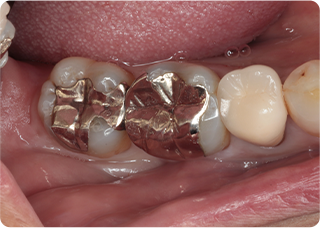

精密根管治療②

術前

術後

| 主訴 | 奥歯で噛むと痛い |

|---|---|

| 治療期間/回数 | 1ヵ月、3回 |

| 価格(税込) | 88,000円(税込) |

| リスク・副作用 | 病変再発、歯根破折の可能性 |

| ポイント | う蝕検知液を用い、むし歯の取り残しが無いようにし、ラバーダム防湿を行い、無菌的に根管治療を行った。根管充填材は、殺菌作用の強い保険適応外のMTAセメントを使用した。 |